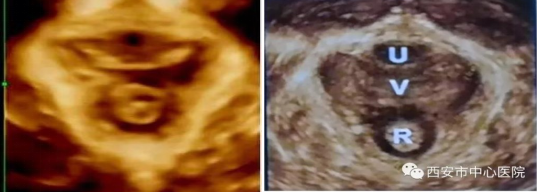

盆底超声检查将盆底肌肉及韧带等结构清晰立体再现,实时动态观察,比较患者静息、缩肛和Valsalva状态盆腔脏器结构和位置改变,直观反映子宫、直肠、膀胱等盆底器官的情况,评估肛提肌裂孔的形态和变化,评估肛提肌及肛门括约肌损伤及程度,在临床症状出现之前做出早期诊断,为临床医生制定合理的治疗方案提供有力依据。